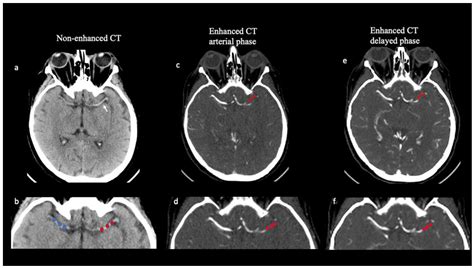

• Emergency Care: Doctors will use imaging (CT scans or MRIs) to identify the nature of the blockage and determine whether the patient is a candidate for clot-busting drugs like tPA.

After the initial emergency, neurologists conduct extensive testing to determine the subtype of the stroke. This is crucial for determining how to prevent a recurrence. Diagnostics may include an echocardiogram to check for heart clots, a carotid ultrasound to check for plaque buildup, and various blood tests to assess clotting disorders. Understanding whether the stroke was thrombotic or embolic dictates whether the physician prescribes antiplatelet medication (like aspirin) or anticoagulants (like warfarin or novel oral anticoagulants).